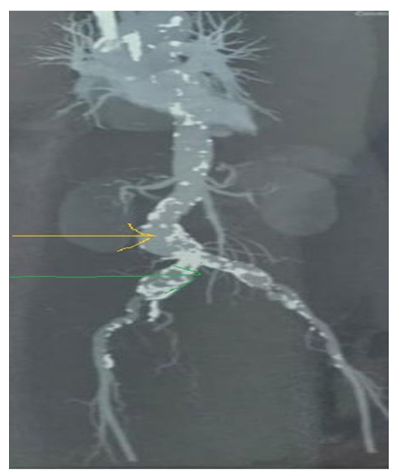

Herpes Zoster Mimmicking Renal Colic

1. Abstract 1.1. Back Ground Herpes zoster, or shingles, is a painful viral infection caused by the reactivation of the varicella-zoster virus (VZV), the same virus as chickenpox, resulting in a blistering rash, often on one side of the body or face, accompanied by burning pain, tingling, and itching.